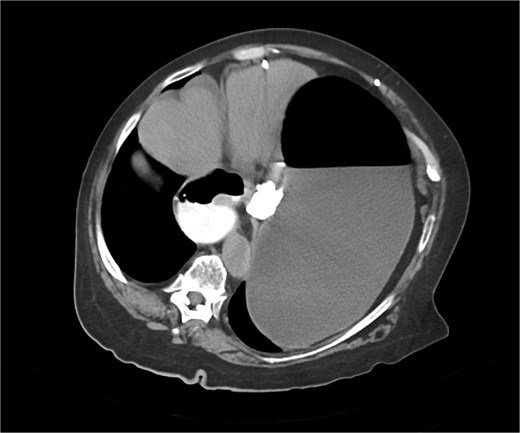

Immediate action involved removing fluid from the gastric band and inserting a nasogastric tube, which was slightly difficult. Only 200 ml of gastric content was drained, and no air was present (indicating that it was not in the stomach). Given the possibility of anatomical pathology or obstruction at the gastroesophageal junction (GEJ), we avoided excessive force when inserting the tube to prevent iatrogenic esophageal perforation. A computed tomography (CT) scan with liquid-soluble contrast media showed that the contrast did not pass beyond the band. The scan also revealed massive gastric dilatation, as well as dilation of the esophagus proximal to the band (Figs 2–4).

CT axial view—contrast media in distal esophagus did not pass to the stomach.